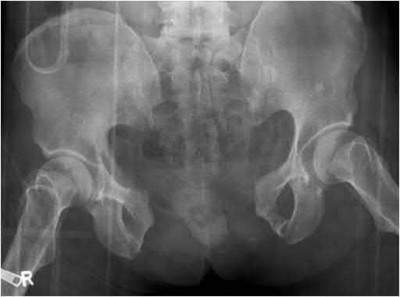

Question 11:

A 6-year-old boy presents with a painless limp of 3 months' duration. His mother notes restricted hip motion, particularly in abduction and internal rotation. Radiographs reveal sclerosis, flattening, and early fragmentation of the proximal femoral epiphysis. In the natural history of Legg-Calvé-Perthes disease, which of the following represents the correct sequence of radiographic stages?

Correct Answer: Initial (necrosis), Fragmentation, Reossification, Healed

Explanation:

The classic radiographic progression of Legg-Calvé-Perthes disease (Waldenström stages) follows four distinct phases: 1) Initial stage (avascular necrosis, sclerosis, and growth arrest), 2) Fragmentation stage (subchondral radiolucent crescent sign, epiphysis fragmenting), 3) Reossification stage (new woven bone formation), and 4) Healed or residual stage (final shape of the femoral head).